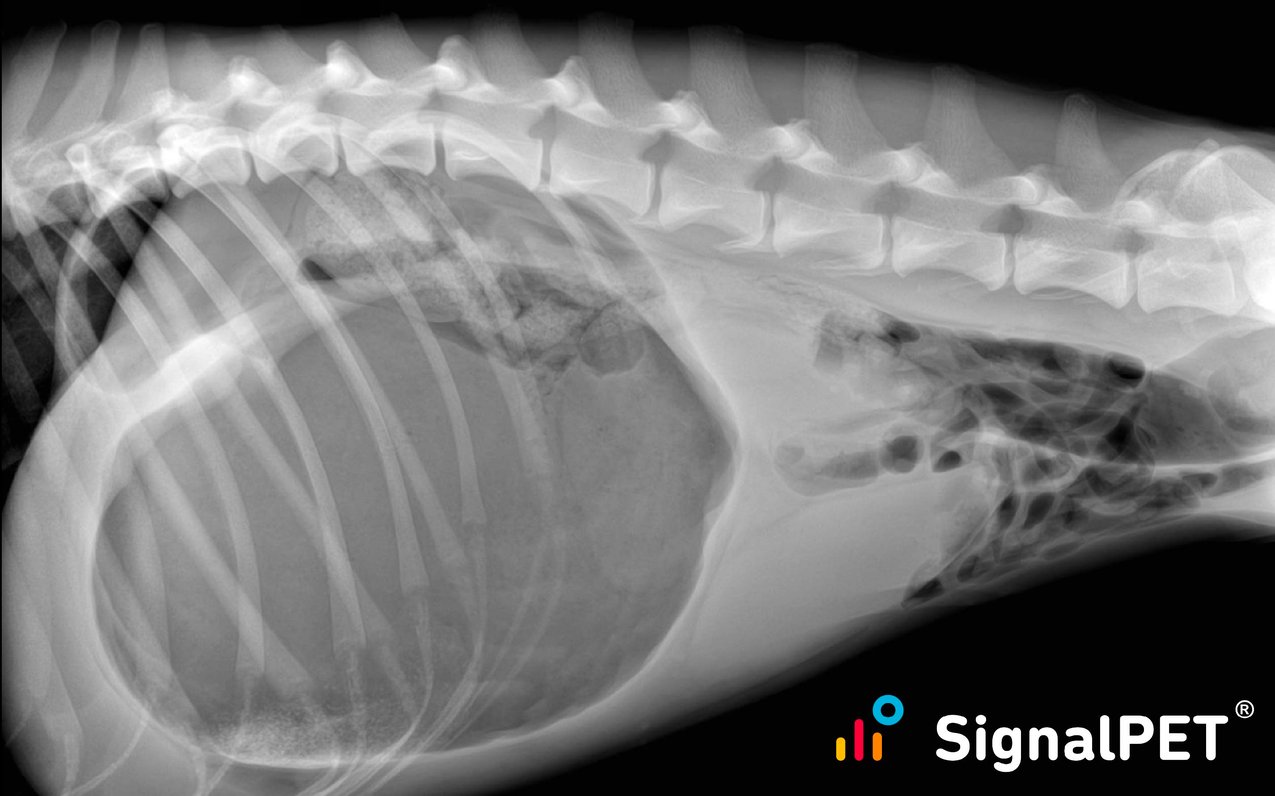

From landing.signalpet.com

Breed all about it A tribute to the Golden Retriever... Bloated Stomach Golden Retriever Excessive gas is not a sign of good health in dogs. It can happen very quickly and should be addressed as an emergency. What is bloat in dogs? Can my golden retriever get bloat? This includes many breeds of dogs, including afghan hound, the basset hound, chow, collie, great dane, irish setter, bernard, weimaraner, standard poodle, and yes, even the. Bloated Stomach Golden Retriever.